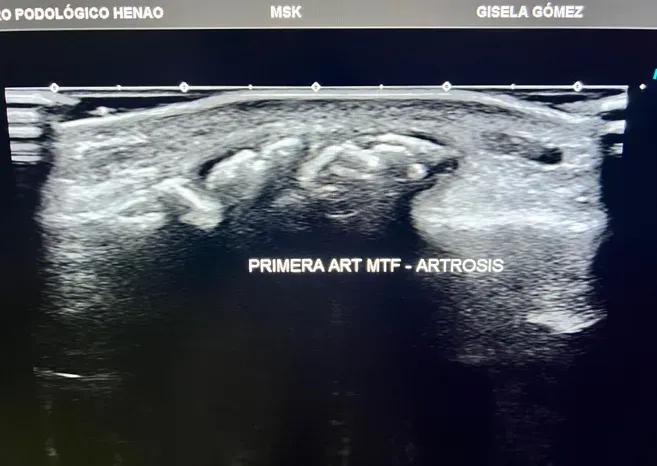

Figura 1: Articulación del pie con signos de artrosis. El desgaste del cartílago provoca fricción, dolor y pérdida progresiva de movilidad.

En el contexto de la artrosis del pie, la ecografía detecta:

- Cambios en el cartílago articular: antes de que la radiografía muestre nada

- Irregularidades en la superficie articular: signos tempranos de desgaste

- Inflamación articular (sinovitis): presencia de líquido o engrosamiento de la membrana sinovial

- Derrame articular: acumulación de líquido dentro de la articulación

- Osteofitos en fases iniciales: formaciones óseas que aún no son visibles en radiografía

- Estado de los tejidos blandos periarticulares: cápsula, ligamentos, tendones adyacentes

Figura 3: Ecografía de una articulación del pie con artrosis. Se observan irregularidades en el cartílago, estrechamiento del espacio articular y formación de osteofitos. Compara con la Figura 2 para apreciar la diferencia.